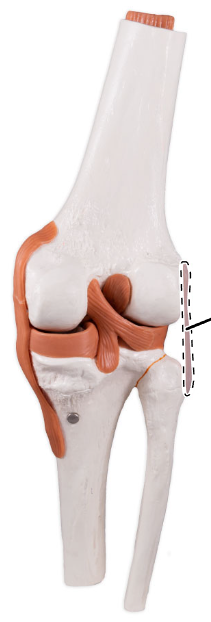

What is the joint shown here?

The tibiofemoral joint.

What is the joint shown here?

The tibiofemoral joint.

Medial (tibial) collateral ligament.

What ligament is shown here?

Medial (tibial) collateral ligament.

Anterior cruciate ligament.

What ligament is shown here?

Anterior cruciate ligament.

What does the anterior cruciate ligament prevent?

The anterior cruciate helps prevent anterior sliding of the tibia.

What ligament is shown here?

Posterior cruciate ligament.

What ligament is shown here?

Posterior cruciate ligament.

What does the posterior cruciate ligament prevent?

The posterior cruciate prevents forward sliding of the femur or backward displacement of the tibia.

What is the highlighted fibrocartilage?

Lateral meniscus.

What is the highlighted fibrocartilage?

Lateral meniscus.

What is the highlighted fibrocartilage?

Medial meniscus.

What is the highlighted fibrocartilage?

Medial meniscus.